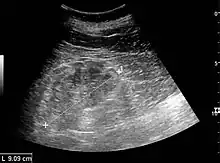

The kidney is divided into parenchyma and renal sinus. The renal sinus is hyperechoic and is composed of calyces, the renal pelvis, fat and the major intrarenal vessels. In the normal kidney, the urinary collecting system in the renal sinus is not visible, but it creates a heteroechoic appearance with the interposed fat and vessels. The parenchyma is more hypoechoic and homogenous and is divided into the outermost cortex and the innermost and slightly less echogenic medullary pyramids. Between the pyramids are the cortical infoldings, called columns of Bertin (Figure 1). In the pediatric patient, it is easier to differentiate the hypoechoic medullar pyramids from the more echogenic peripheral zone of the cortex in the parenchyma rim, as well as the columns of Bertin (Figure 2).[1]

The length of the adult kidney is normally 10–12 cm, and the right kidney is often slightly longer than the left kidney. The adult kidney size is variable due to the correlation with body height and age; however, normograms for pediatric kidney size are available.[1]

Cortical thickness should be estimated from the base of the pyramid and is generally 7–10 mm. If the pyramids are difficult to differentiate, the parenchymal thickness can be measured instead and should be 15–20 mm (Figure 3). The echogenicity of the cortex decreases with age and is less echogenic than or equal to the liver and spleen at the same depth in individuals older than six months. In neonates and children up to six months of age, the cortex is more echogenic than the liver and spleen when compared at the same depth.[1]